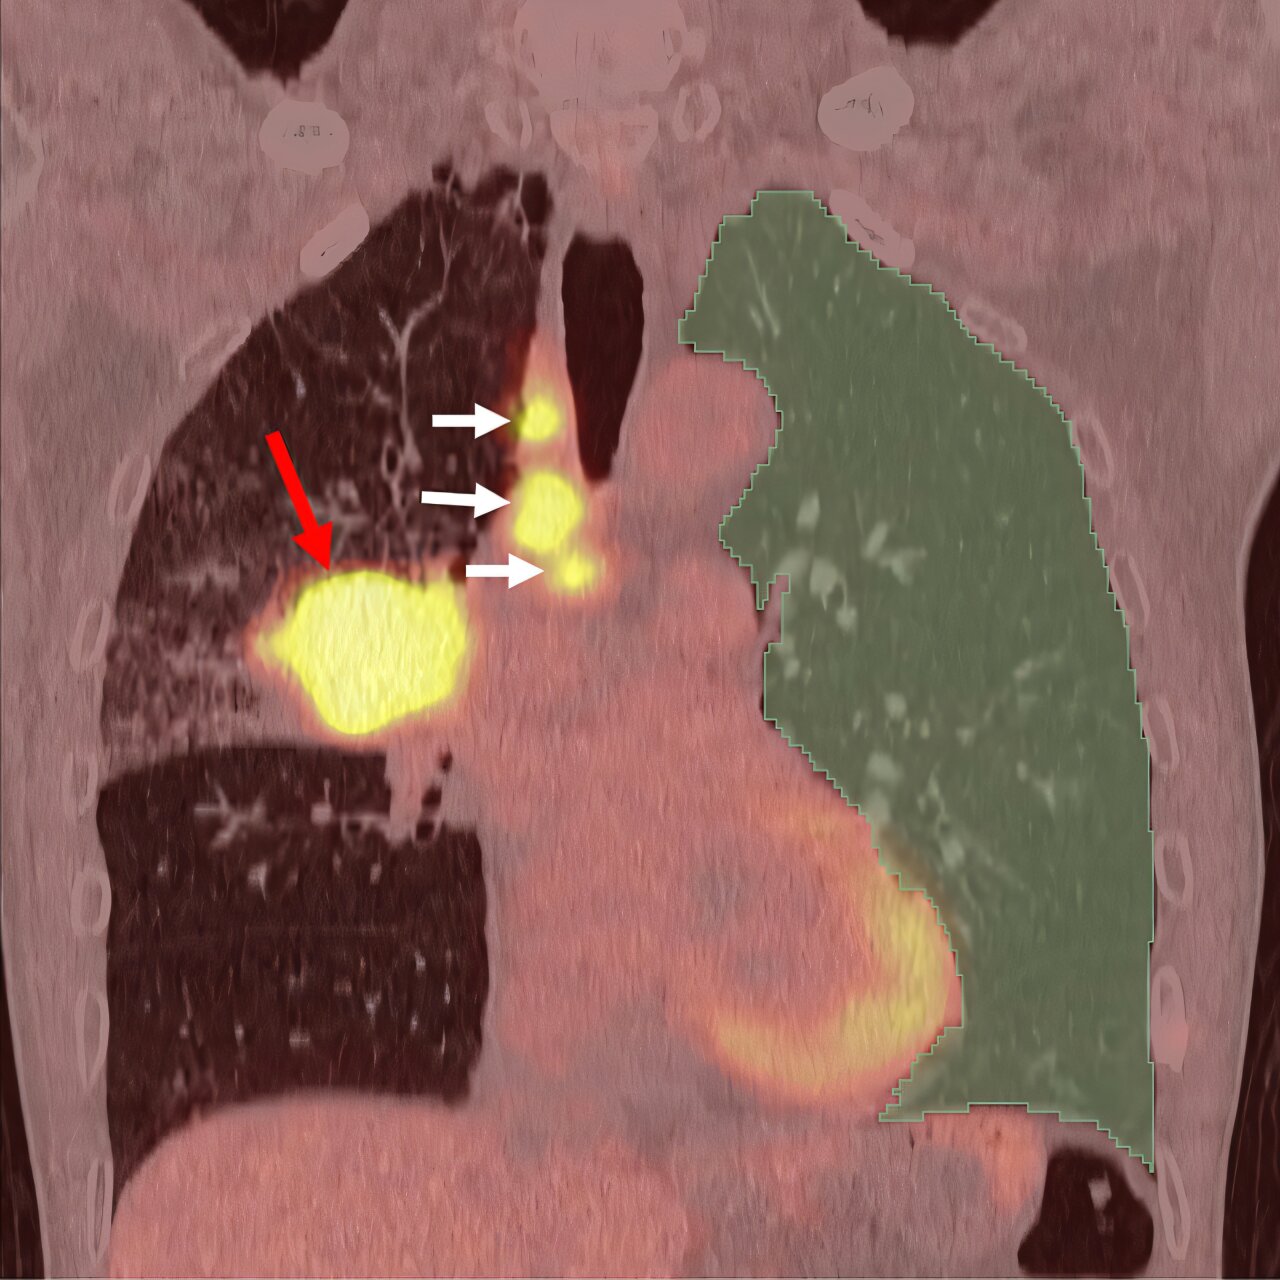

この課題に直面して、新潟大学の科学者たちは、免疫療法を受けている肺がん患者における PID の発生を予測できる AI システムを開発しました。この AI システムは、PET/CT 画像解析を使用して肺の非癌領域の炎症を評価し、PID を発症するリスクが最も高い患者を特定します。

方法論と調査結果

この後ろ向き研究には、新潟大学医歯学病院で治療を受けた原発性肺がん患者165人が含まれた。炎症を検出できるPET/CT画像を用いて、AIシステムががんの影響を受けていない肺領域の炎症の程度を数値化した。その結果、高レベルの炎症を有する患者は、低レベルの炎症を有する患者に比べて、免疫療法後にPIDを発症するリスクが約6.5倍であることが示された。

将来への影響

この進歩は、治療法を選択する前に副作用のリスクを推定するために使用できる予測ツールを提案するだけでなく、PID の根底にあるメカニズムを理解するための新しい窓も提供します。炎症細胞ががん細胞と健康な細胞の両方をどのように活性化して損傷するかを理解することは、より効果的で安全な治療戦略を開発するための鍵となる可能性があります。